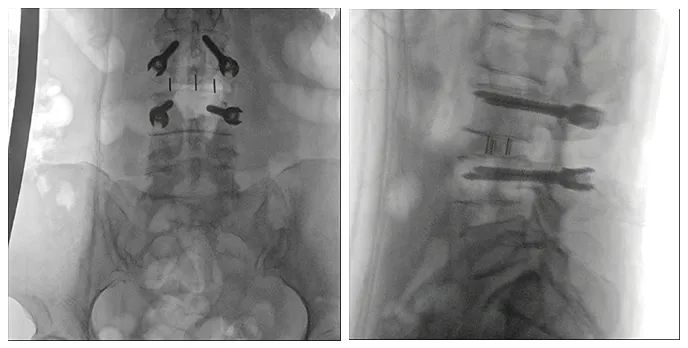

使用普愛醫療術中三維導航C臂進行透視,根據透視影像引導確認責任間盤、規劃手術方案,充分暴露骨組織,并通過專業器械切除椎板,暴露神經及椎管;在C形臂的引導下,確定責任間盤上下椎體椎弓根位置,制定進針點及進針方向,沿椎弓根方向植入脊柱螺釘進行固定;放入椎間融合器,加固螺釘。最后再進行C形臂透視,確認手術的完成效果。

手術效果確認